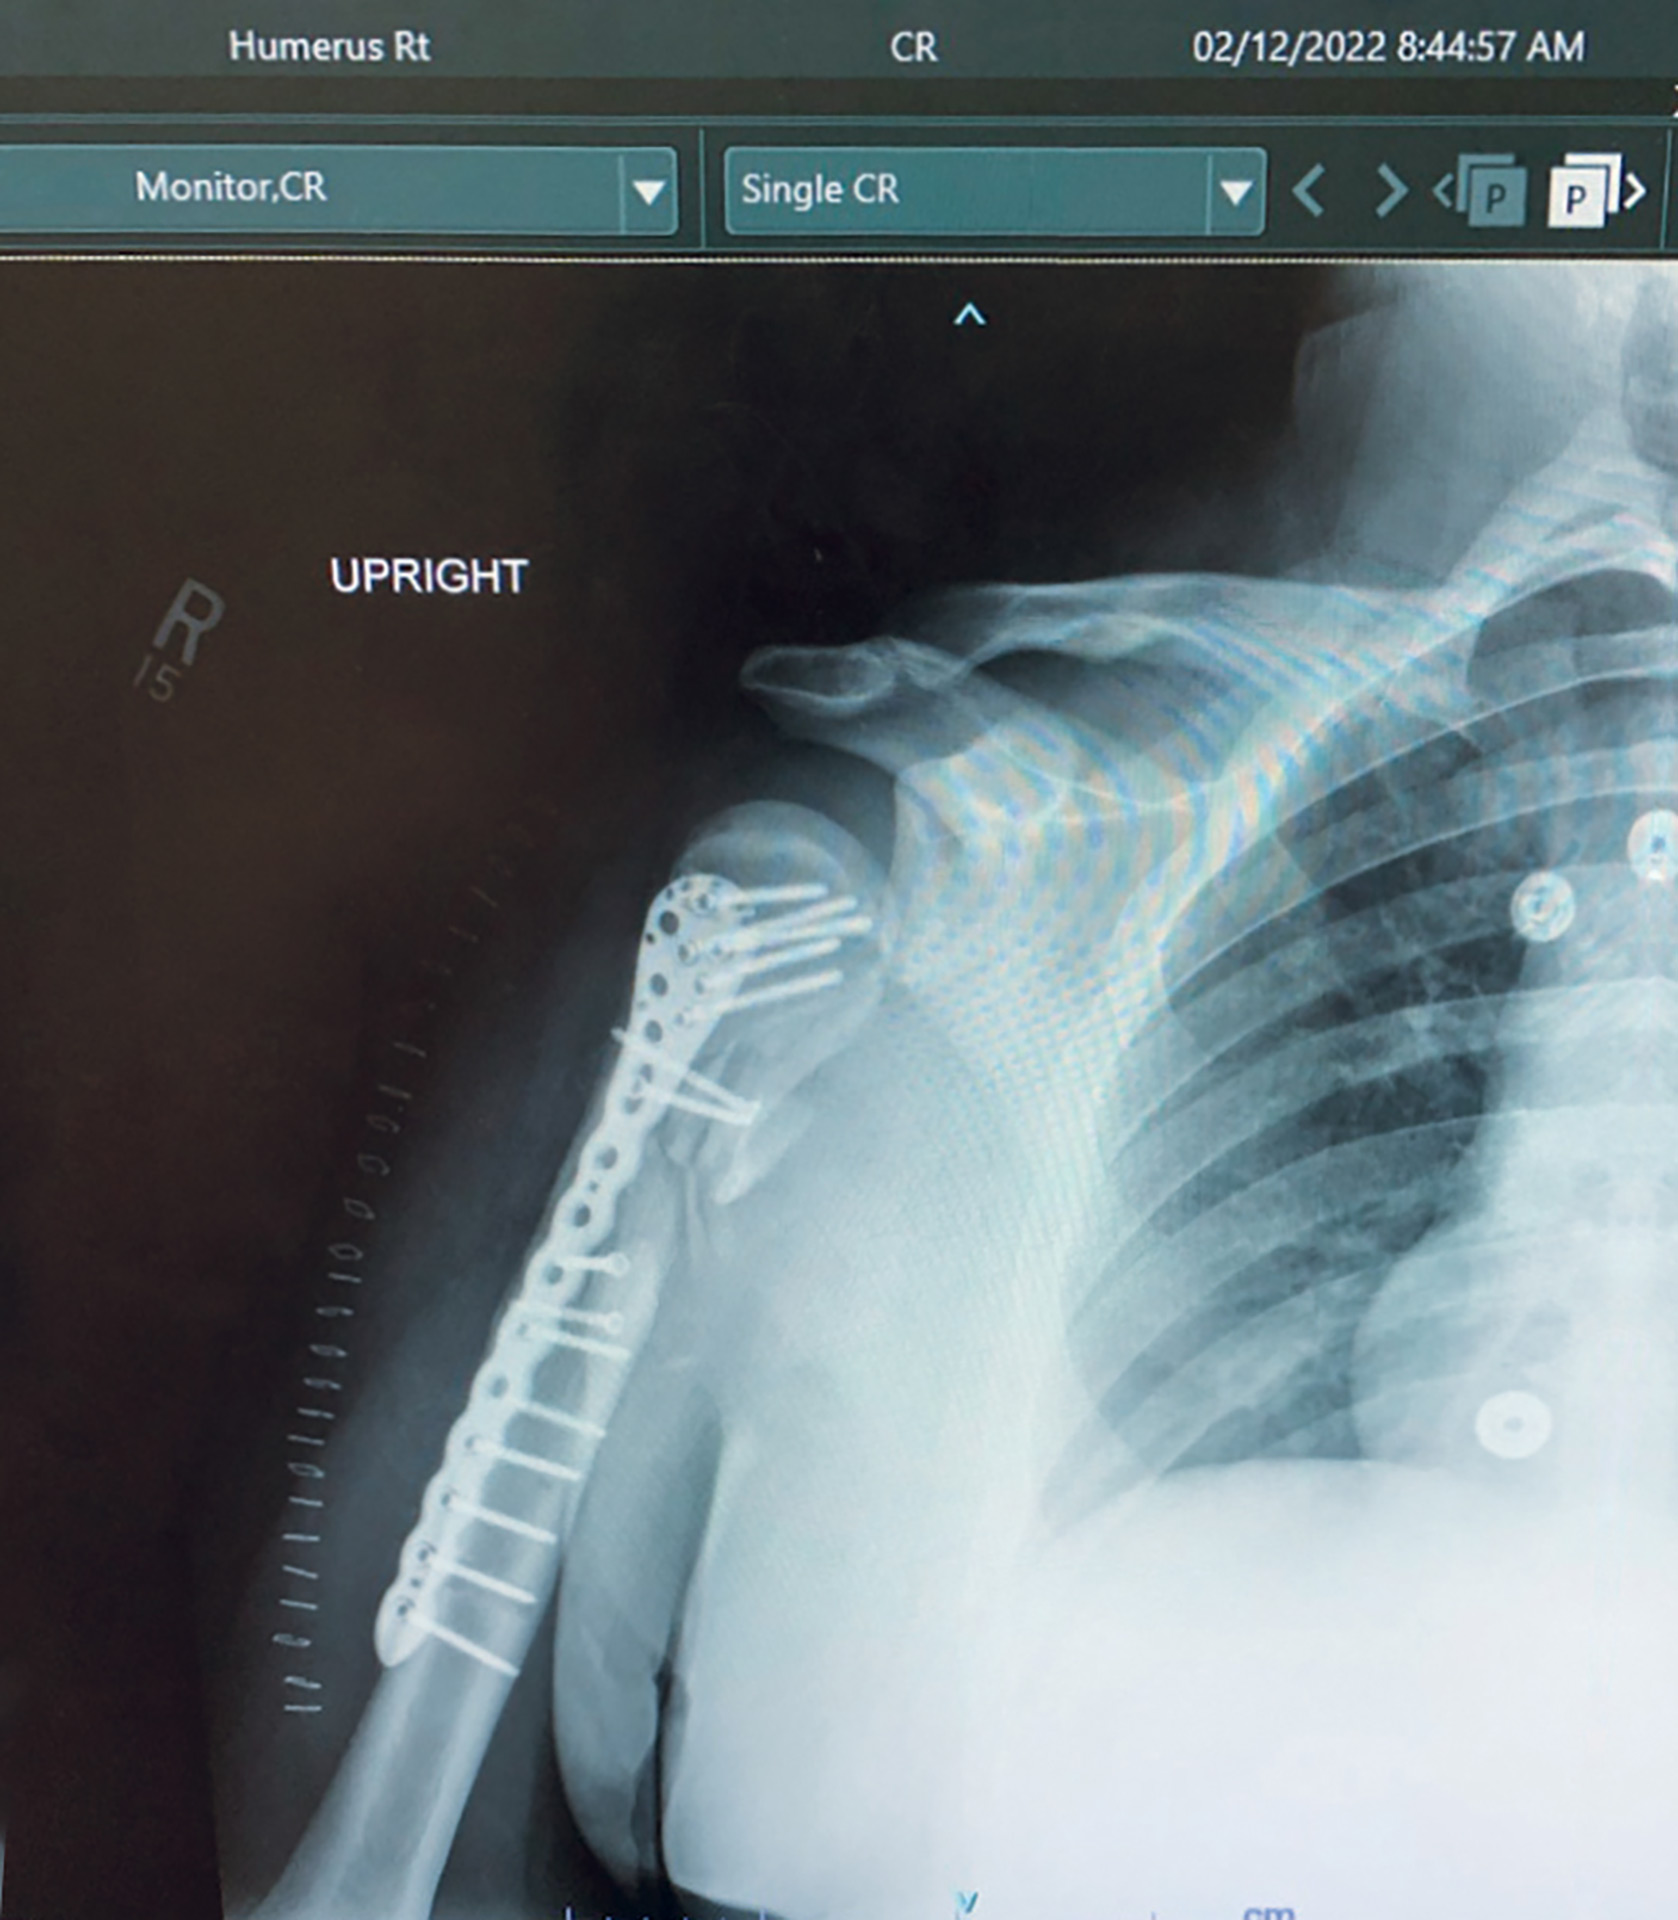

Austin later woke up in a hospital room with his family surrounding him. It was in this moment that he was so thankful to be alive. He was shot five times in total. He was shot in his right forearm through and through; right upper arm, which shattered the humerus bone; right upper chest front, which exited his back, fracturing his shoulder blade; right lateral area through and through; and left hand through and through. The most severe injury was to his humerus bone, which needed immediate surgery. The doctors had to cauterize the injuries to stop the bleeding.

Austin says that his right arm bone is still healing and that his arm is able to function. There is still nerve damage, which is consistent with his injuries, that affects his hand function. Doctors placed a metal plate and 15 screws to reconstruct the bone in his right arm. The other injuries have healed, but there is still some sensitivity around the injury sites. The first month or so was difficult because he could not get sleep due to pain. He has returned to work on light-duty status, with a lot of doctor’s appointments. He is still recovering physically and mentally from the trauma of that day. I asked Austin how he feels now, and he said, “I am so thankful for my family for being there and my fiancée, Brooke.” He is looking forward to getting back into hunting, fishing and playing golf again. He wanted to thank his friends who have always been around when he needed them. He wants to tell his story and let the newer officers know: “Don’t give up, and refuse to lose. You need to bounce back from stuff like this.” Austin has completed detective school and general instructor school, and is looking toward the future of possibly being an instructor at the Academy or even the Employee Assistance Unit (EAU) to help his fellow officers. “Considering the circumstances, I feel very lucky,” he says.